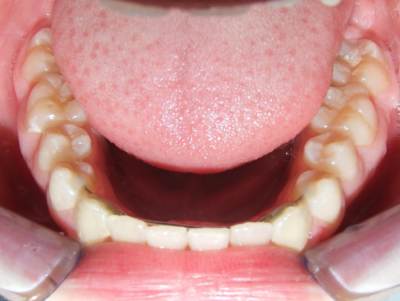

Behandeling Raoul

eindfoto

Leeftijd bij aanvang: 10 jaar

Bonded Hyrax + volledig vast onderkaak

Volledig vast bovenkaak + expander

Wrap + c-c bar onderkaak

Leeftijd bij afname: 12 jaar